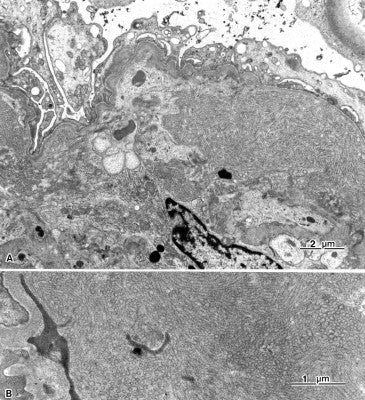

新版 腎生検アトラス 腎組織からみた治療へのアプローチ/医歯薬出版。商品詳細ページ | メディカルブックセンター。腎癌 | 株式会社文光堂。「腎生検病理アトラス」日本腎臓学会 / 日本腎病理協会定価: ¥ 10000#日本腎臓学会 #日本腎病理協会 #本 #自然/医療・薬学・健康【概要・注意】 確認した限りでは書き込みはありませんが、見落としや多少の折り目等の使用感含めてご了承頂ける方のみよろしくお願いいたします。なお、裁断前商品と取り違えて購入した場合には一切の返品対応を致しません。。ジョーシキ!腎病理診断エッセンシャル | 城 謙輔, 原 重雄 |本 | 通販。裁断済のため「全体的に状態が悪い」としています。[NICOさん専用]病気がみえる 全10巻セット【個別売り可】。ザ・メタルセラミックス 山本眞箸 歯科 歯科技工。よくご確認いただいた上で、購入をご検討ください。※裁断済み GPが行う矯正治療を組み入れた咬合再構成お店の情報